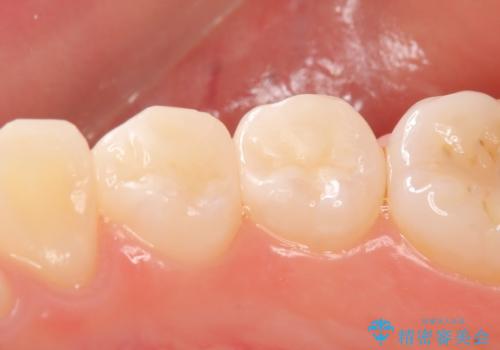

- 右下の4、5番目の歯がしみるといらっしゃった方の症例です。

右下4の遠心及び右下5の近心部が痛むとのことだったので、虫歯除去後、セラミックインレーによる修復を行いました。